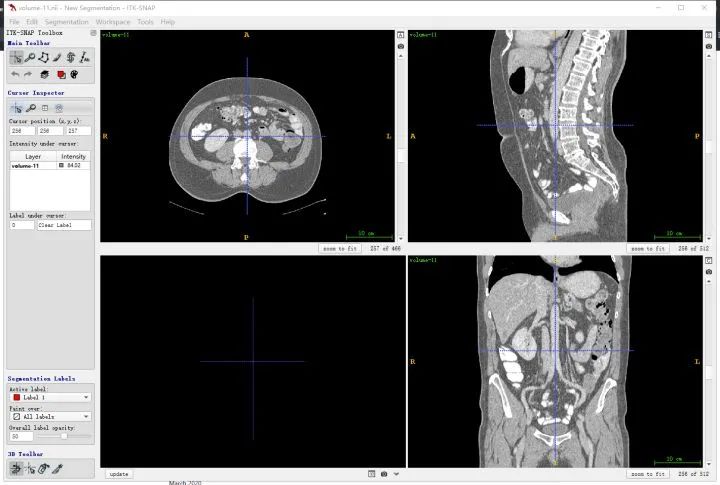

In ITK-SNAP the same slice is shown at coordinates (x,y,z) = (256,256,101) because ITK-SNAP uses 1-based indexing by default.

The X axes match between the two displays, but the Y axis is flipped due to differences in matplotlib display conventions. This does not indicate a mismatch in the loaded data.